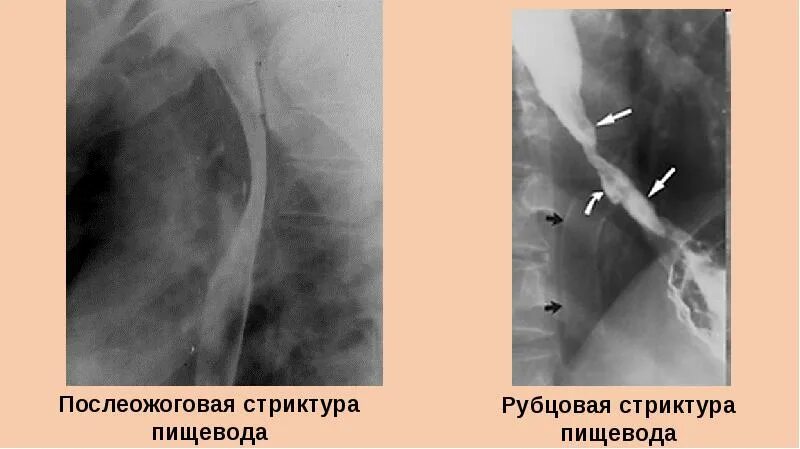

Стеноз пищевода симптомы